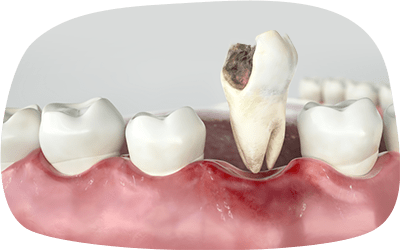

虫歯を放置すると

どうなる?

感染が顎骨に広がり、骨が溶け最悪の場合、抜歯が必要になる場合があります。

全身に悪影響を及ぼす可能性があるため、早めの治療が必要です。